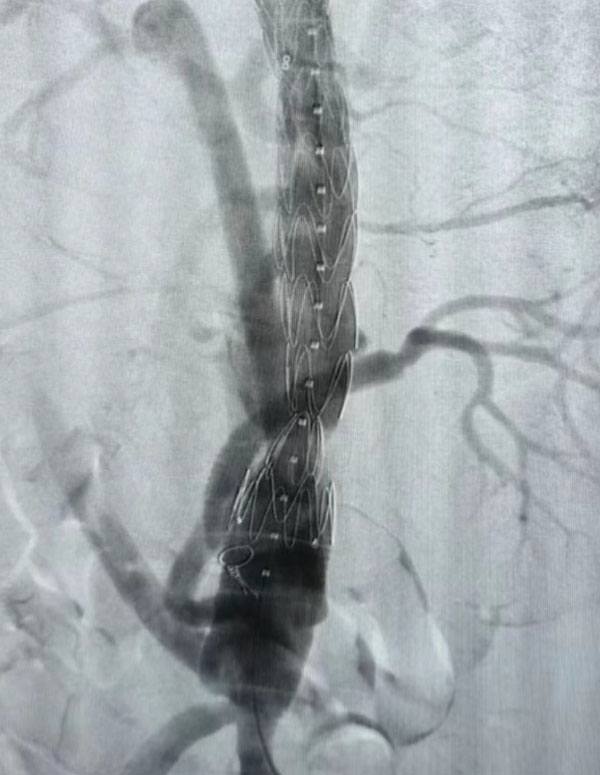

同期,另一台“升主动脉置换+全主动脉弓置换+胸主动脉覆膜支架腔内隔绝术”正在开展,该病例为一名A型主动脉夹层患者。在主动脉弓及分支成功游离且心脏停跳后,心外科负责人赵永波“转场”为患者完成了血管置换,心脏复跳成功,止血彻底。随后,谈凌凌主治医师、侯五辉主治医师为患者进行胸主动脉腔内修复。下午2点左右,两台手术成功结束。通过现场视频直播,在手术同时,手术人员与大会现场的专家们就影像评估、手术策略、手术器械的选择及操作技巧等多个环节进行了互动讨论,学术气氛热烈,大会主席及与会代表给予我院高度评价。紧接着,手术团队又为一名79岁腹主动脉瘤患者进行了腹主动脉腔内修复手术,效果良好,同样受到与会专家的好评。

全主动脉弓置换